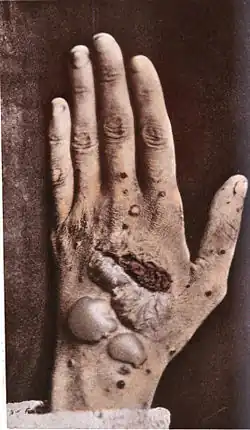

The several types of pemphigus (pemphigus vulgaris, pemphigus foliaceus, intraepidermal neutrophilic IgA dermatosis, and paraneoplastic pemphigus) vary in severity. Skin lesions caused by pemphigus can lead to fatal infections, so treatment is extremely important.

- Pemphigus vulgaris (PV - ICD-10 L10.0) is the most common form of the disorder and occurs when antibodies attack desmoglein 3. Sores often originate in the mouth, making eating difficult and uncomfortable. Although PV may occur at any age, it is most common among people between 40 and 60. It is more frequent among Ashkenazi Jews. Rarely, it is associated with myasthenia gravis. Nail disease may be the only finding and has prognostic value in management.[8]

- Pemphigus foliaceus (PF) is the least severe variety. Desmoglein 1, the protein that is targeted by the autoantibodies, is enriched in the upper skin layers. PF is characterized by crusty sores that often begin on the scalp, and may move to the chest, back, and face. Mouth sores do not occur. This form is also frequent among Ashkenazi Jews. It is not as painful as PV, and is often misdiagnosed as dermatitis or eczema[8] PF is endemic in Brazil [9] and Tunisia.[10]

- The least common and most severe type of pemphigus is paraneoplastic pemphigus (PNP). This disorder is a complication of cancer, usually lymphoma or Castleman's disease. It may precede the diagnosis of the tumor. Painful sores appear on the mouth, lips, and the esophagus. In this variety of pemphigus, the disease process often involves the lungs, causing bronchiolitis obliterans (constrictive bronchiolitis). Though much less frequent, it is still found the most in the Ashkenazi Jewish population. Complete removal of and/or cure of the tumor may improve the skin disease, but lung damage is generally irreversible.

Animals affected

Pemphigus foliaceus has been recognized in pet dogs, cats, and horses, and is the most common autoimmune skin disease diagnosed in veterinary medicine. PF in animals produces clusters of small vesicles that quickly evolve into pustules. Pustules may rupture, forming erosions or become crusted. Left untreated, PF in animals is life-threatening, leading to not only loss of condition, but also secondary infection.